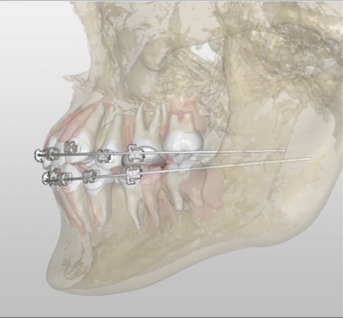

本教学团队已将虚拟仿真教学引入口腔正畸的理论授课和实践教学,初步构建了虚拟仿真诊疗场景和标准化患者。本团队在此基础上,进一步开发“口腔正畸生物力学可视化诊疗操作虚拟仿真实验”,具有两大特征,即正畸支抗技能训练和生物力学相关牙移动可视化。种植支抗在正畸临床应用中较为常见,因其临床操作具有不可逆性和有创性,临床前实践技能培训显得尤为重要。正畸支抗技能训练以种植支抗为例,包括构建正畸种植支抗植入手术术前沟通、术中操作及术后效果评价等模块,理解正畸生物力学中支抗的概念和相关操作要点。生物力学相关牙移动可视化是指基于生物力学机制,借助虚拟仿真系统,通过学生设计不同的矫治力系统(种植支抗位置、牵引钩类型及位置等),展示矫治力线与牙齿阻抗中心、旋转中心的相互关系,模拟不同牙移动类型,帮助学生更好地理解生物力学的相关概念和实际应用原理。

在“生物力学设计与牙移动可视化展现”虚拟训练模块,包括选择种植支抗位置、牵引钩类型及位置等,设计不同的矫治力系统;基于已设计的矫治力系统,生成相应的牙移动动画,实现基于生物力学的牙移动可视化教学。

本项目借助 Unity 3D、Studio Max 等工具构建虚拟患者及其牙移动过程,基于复旦大学口腔医学院正畸教研室的临床真实病例,高度模拟还原牙、牙根及牙槽骨等生物学结构。学生进行矫治力支点、方向的设计和制定,形成特定的正畸矫治力系统。通过虚拟动画展示在该系统下的牙移动方式,可视化展示作用力线与牙齿的旋转中心、阻抗中心之间的相互关系对牙齿移动类型的影响,有助于学生理解生物力学相关基本概念及其在临床实践中的应用。

步骤7 进入牙移动操作界面,按照规定的牙移动类型,完成上前牙区牵引钩类型、位置的选择

步骤8 在牙移动操作界面,观看牙移动过程及生物力学机制